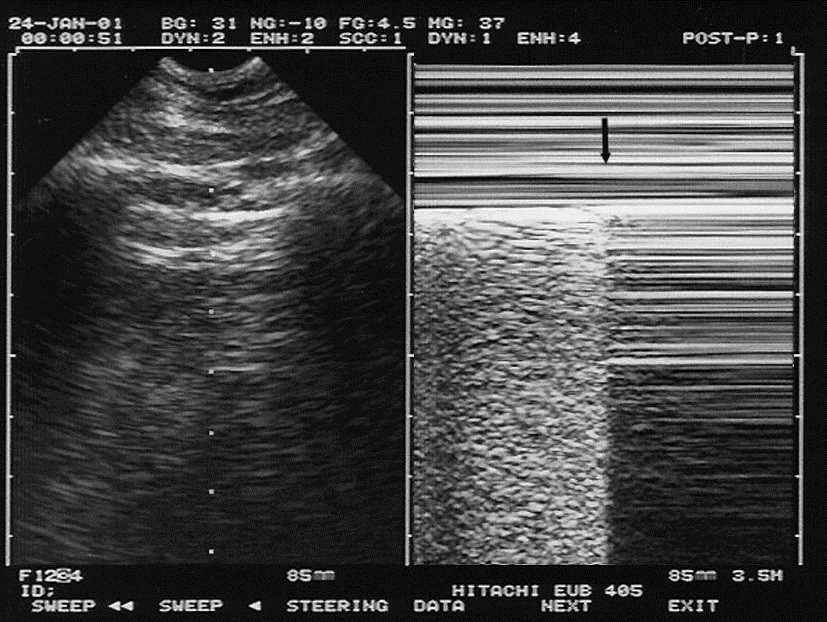

M-mode m mode sono (motion mode) ultrasound m-mode is defined as a motion versus time display of the b-mode ultrasound image along a chosen line. the motion is represented by the y-axis and time is represented by the x-axis. Feb 22, 2019 often utilized for its excellent axial and temporal resolution of structures, m-mode (or motion mode) is a form of ultrasonography in which .

Movement of structures positioned in that line can now be visualized; often m-mode and b-mode are displayed together in real-time on the ultrasound monitor . M-mode (or motion mode), is a technique that previously was taught to be useful in the evaluation of a ptx. in fact, many publications that speak on the topic report that m-mode is a useful adjunct in the evaluation of a ptx. 5,10-13 (update: 7/3/18). previously, i was pretty much a hater for using m-mode in the evaluation of a pneumothorax. Der m-mode ist ein darstellungsverfahren der sonographie. hierbei wird eine einzelne schallzeile mit hoher wiederholungsfrequenz erzeugt und über die zeit . (2d), includes m-mode recording, when performed, during rest and cardiovascular stress test using treadmill, bicycle exercise and/or pharmacologically induced stress, with interpretation and report; including performance of continuous electrocardiographic monitoring, with physician supervision.

The m-mode provides i-d information along the beam path. it should be noted that for a moving structure to be detected, it must lie along the ultrasound beam . M-mode: in m-mode (motion mode), pulses are emitted in quick succession each time, either an a-mode or b-mode image is taken. over time, this is analogous to recording a video in ultrasound. as the organ boundaries that produce reflections move relative to the probe, this can be used to determine the velocity of specific organ structures. I’ve also created several tools to aid ultrasound directors: a script that de-identifies ultrasound clips and an online m. mode. ify tool that can be used to create an m-mode image from any clip. i’ve completed the acep teaching fellowship and my interests include landscape photography, digital image manipulation and computer coding. Non-sonosite product names may be trademarks or registered trademarks of their toggles between dual and duplex screens and imaging modes in m mode.

Imaging mode transducer exam type 1 2d2 m mode cpd3 color3 pw doppler c60x hfl38x hfl50x l25x l38xi slax msk 1. msk = musculoskeletal 2. the optimization settings for 2d are res, gen, and pen. 3. the optimization settings for cpd and color are low, medium, and high (flow sensitivity) with a range of prf settings for color depending on the. M-mode (ultrasound) often utilised for its excellent axial and temporal resolution of structures, m-mode (or motion mode) is a form of ultrasonography in which a single scan line is emitted, received, and displayed graphically. an m-mode recording is conventionally displayed with the abscissa representing time and the ordinate distance from the.